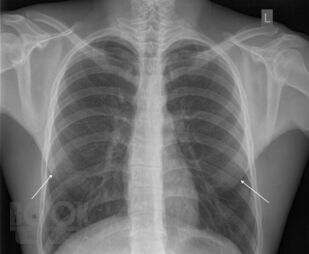

Рентгеноанатомия органов грудной клетки

Губик Е. А. Рентгеноанатомия органов грудной клетки : Учебное пособие / Е. А. Губик, Т. В. Кузина. - Чита : Издательство ЧГМА, 2023. - 76 c. - Текст : электронный // ЭБС "Букап" : [сайт]. - URL : https://www.books-up.ru/ru/book/rentgenoanatomiya-organov-grudnoj-kletki-16748814/ (дата обращения: 26.05.2026). - Режим доступа : по подписке.

В данном электронном пособии систематизированы и подробно изложены сведения о рентгеновской анатомии органов грудной клетки.